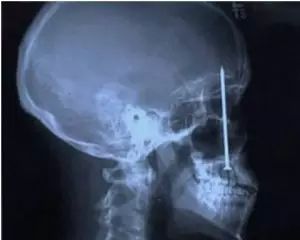

6.这是2008年一宗谋杀案,尸体被发现在公寓被子弹击中头部。透视检查过后发现,他是被射钉枪打死的

这是2008年一宗谋杀案,尸体被发现在公寓被子弹击中头部。透视检查过后发现,他是被射钉枪打死的